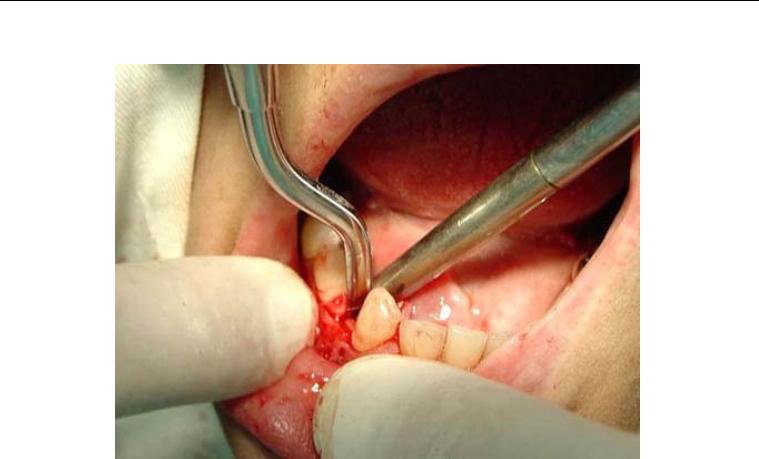

Foi no intuito de transpor estas dificuldades que se idealizou o sistema de

implante inicialmente conhecido como Wedge (figura 1) e que, após dez anos de